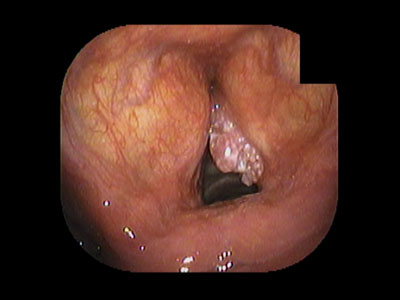

くさの耳鼻咽喉科・小児科では内視鏡を積極的に使用して、

耳・鼻・のどの普段は見えない部分を患者様やご家族の皆さんに実際に見ていただいています。

「見える」は「わかる」!「わかる」ことで「治す」が加速する!

実際の内視鏡画像を見ながら病気の経過を知れば、あなたも今日から鼓膜ハカセ!?